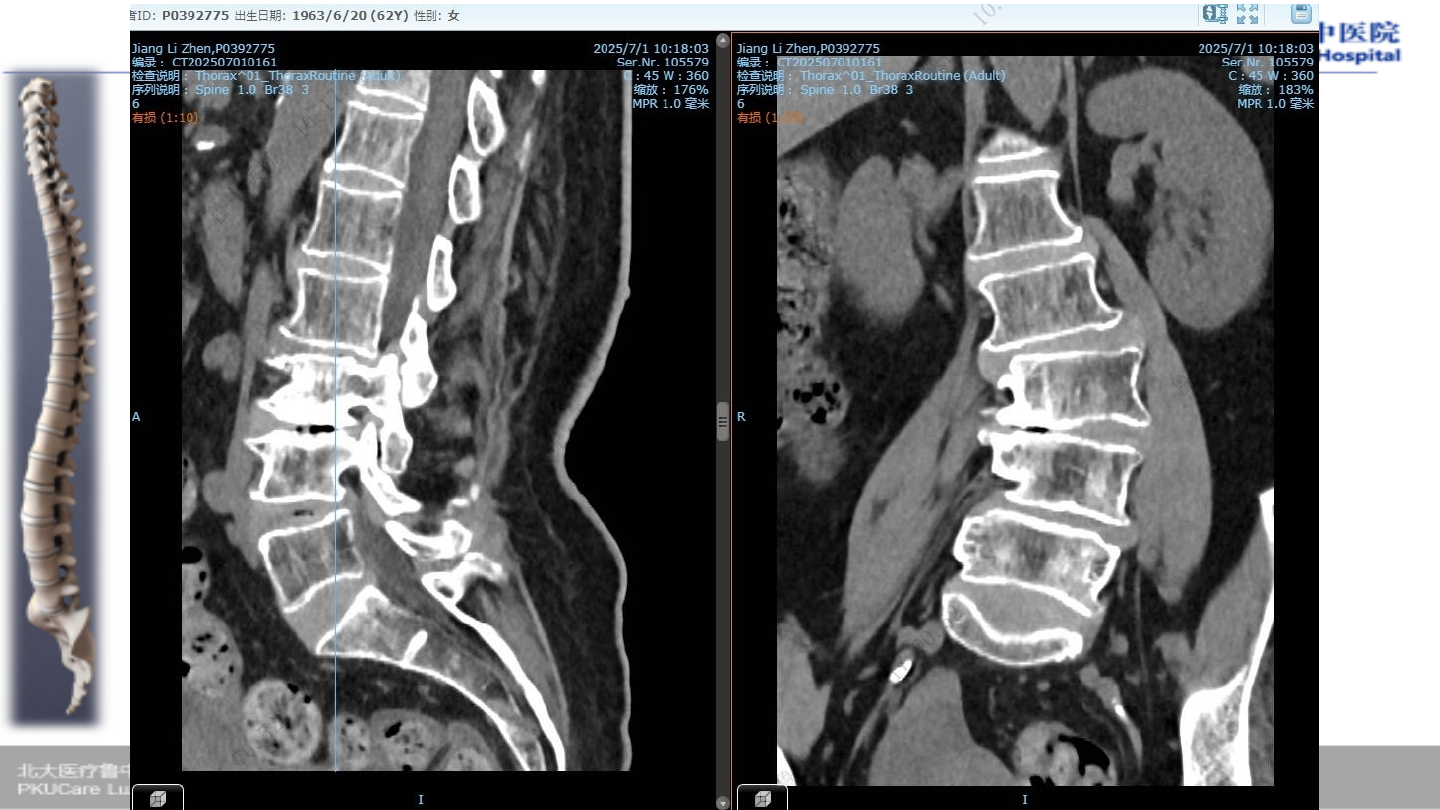

术前腰椎

X-ray